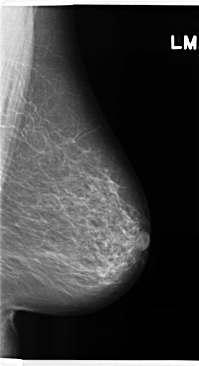

C_0278_1.LEFT_MLO

LEFT_MLO LINES 4752 PIXELS_PER_LINE 2584 BITS_PER_PIXEL 12 RESOLUTION 50 NON_OVERLAY